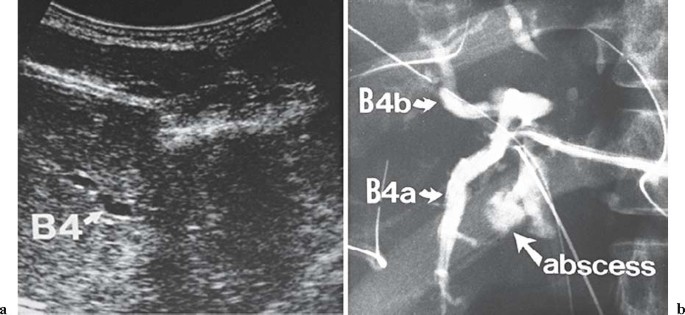

When a patient with hilar cholangiocarcinoma who has already undergone biliary drainage suddenly presents with high fever, the most probable cause of the fever is cholangitis due to drainage catheter obstruction or catheter dislodgement, or segmental cholangitis in the undrained segment (Fig. 1). If cholangiography demonstrates no problem with the existing catheter, segmental cholangitis should be suspected. After giving antibiotics and identifying the undrained bile duct by computed tomography (CT) or ultrasonography (US), drainage must be urgently performed in the undrained segment24,25(level V). Even with a wait-and-see approach when using antibiotics, drainage should be considered if the fever does not come down within 1 or 2 days. Drainage can become effective either through the additional insertion of a new PTBD catheter or, if possible, through inserting the existing catheter into the undrained bile tract.23,25,26 The latter method is less invasive and less painful for the patient. If drainage is done properly, the fever comes down by the following day in most patients, and administration of antibiotics for 2 or 3 days is sufficient27 (level IV).

Fig. 1a,b

A patient who had undergone percutaneous transhepatic biliary drainage (PTBD) suddenly presented with high fever. a Abdominal ultrasound demonstrated dilation of the left medial segmental bile duct (B4). A diagnosis of segmental cholangitis of this undrained segment was made, and additional PTBD was performed urgently. b Cholangiogram through the PTBD catheter shows typical findings of liver abscess